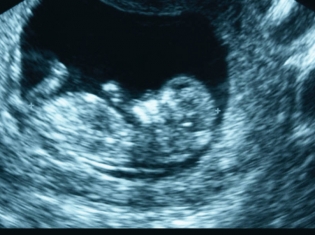

A recent study, however, has found a method that might help establish a baby's risk of autism at birth.

This study found that the placentas of women who already had at least one child with autism were much more likely to have certain abnormal creases.

The number of creases in a woman's placenta appears to predict how high a child's risk of developing autism might be.

The researchers specifically looked for abnormal folds, or creases, in the major cell type of the placenta, called trophoblasts.

These abnormal creases are called trophoblast inclusions.

The researchers found that the placentas from the families with autism were eight times more likely to have two or more trophoblast inclusions compared to the placentas from women with only typically developing children.

The placentas from the families with autism had up to 15 trophoblast inclusions, but none of the placentas from the control families had more than two of these abnormalities.

In fact, 92 percent of the placentas from the women with no autistic children had only one trophoblast inclusion or none at all.

The researchers calculated that a placenta with four or more of these abnormalities predicted the baby had a 74 percent probability of being at risk for autism.

Identifying these abnormalities in the placenta "has the possibility of identifying newborns at risk for autism spectrum disorders who might benefit from targeted early interventions aimed at preventing or ameliorating behavioral symptoms and optimizing developmental outcomes," the researchers wrote.